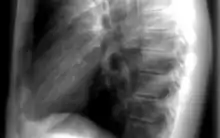

Les informations provenant des différentes structures traversées par le faisceau de rayonnements sont projetées sur un même plan pour former l'image. Par conséquent, il est souvent nécessaire de réaliser deux projections, à différentes incidences, pour pouvoir localiser une structure dans les trois dimensions de l'espace. Par exemple, en médecine, il s'agit fréquemment d'incidences de face et de profil. La loi d'atténuation des photons explique l'atténuation différentielle du faisceau à travers différentes structures, ce qui est à l'origine du contraste radiographique.